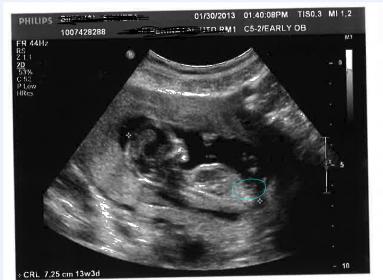

These were taken at 13w3D

What is the circled part?

Is there any nub? what about skull theory?

thanks Inky. So what is that white thing in the bottom? I thought that was nub.